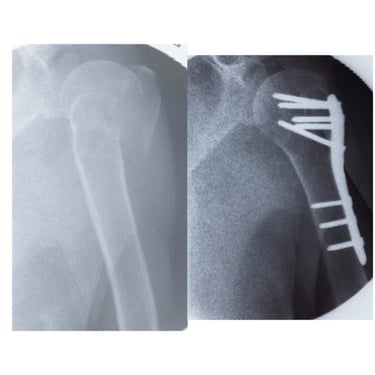

Paciente fémina de 70 años de edad, muy activa e independiente, presenta fractura de húmero proximal multifragmentada. Se opta por tratamiento quirúrgico en el cual se obtienen resueltados excelentes. Actualmente en fisioterapia y realizando actividades de la vida diaria sin limitaciones

FRACTURA DE HUMERO PROXIMAL